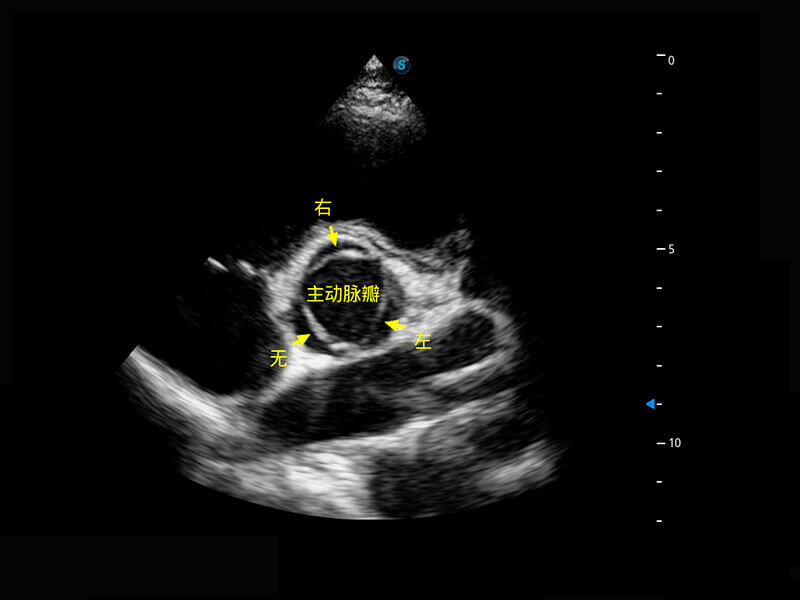

P60搭載一系列胎兒心臟成像技術(shù),實現(xiàn)精細的胎兒心臟評估。

四腔切面

右室雙出口